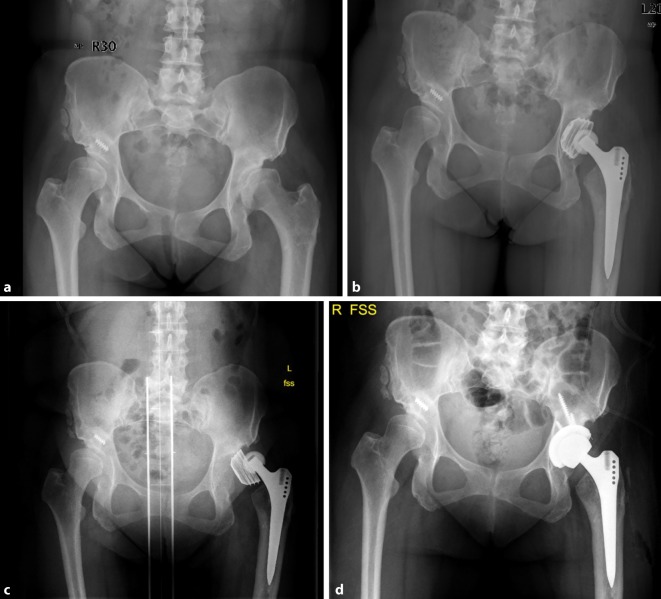

Fig. 2.

AP X‑rays of the hip (a) of a 62-year-old female patient with left-sided dysplasia and coxarthrosis, b primary THA in an external hospital, c loosening and dislocation of the acetabular cup, d revision of the acetabular cup of type I acetabular bone defect using a cementless press-fit hemispherical acetabular cup with additional screw fixation (Mathys AG). (Courtesy of the Department of Diagnostic and Interventional Radiology, University Hospital of Leipzig, all rights reserved)